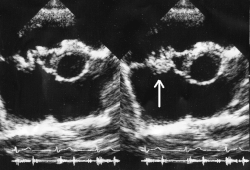

![]() Вегетации митрального клапана при инфекционном эндокардите. | |

Важное условие развития ИЭ — повреждение эндокарда или эндотелия, которое может возникать в результате пороков клапанов, микротравм, операции, проникновения инородных тел и др. К повреждённому эндотелию прикрепляются тромбоциты, образуется небольшой, первоначально стерильный тромб. Затем такой тромб инфицируется различными возбудителями, циркулирующими в крови. Таким образом формируется вегетация, состоящая из бактерий, фибрина, лейкоцитов и тканевого детрита. Вегетация — характерный признак ИЭ, обнаруживаемый при Эхокардиоскопии. Сами бактерии также способны напрямую повреждать клапаны сердца с образованием различных дефектов, фистул и абсцессов.

Окончательный диагноз устанавливают при получении положительных результатов посева крови и данных об обнаружении вегетаций при эхокардиографии.

Эхокардиография

Среди различных визуализирующих исследований методом выбора считают ЭхоКГ. Её результаты служат основой для дальнейшего ведения пациента. Доказано, что в отношении выявления вегетаций, деструктивных осложнений и абсцессов транспищеводная ЭхоКГ обладает большей чувствительностью по сравнению с трансторакальной ЭхоКГ . При серьёзных клинических подозрениях на эндокардит и неубедительных или отрицательных данных трансторакальной ЭхоКГ следует проводить транспищеводное исследование. Напротив, отрицательные данные транспищеводной ЭхоКГ в значительной степени ставят под сомнение диагноз ИЭ. Тем не менее при сохранении существенных клинических признаков (например, при положительном посеве крови и выделении типичного возбудителя) транспищеводную ЭхоКГ следует повторить через несколько дней, особенно при наличии предрасполагающих заболеваний сердца (например, при протезе клапана сердца). Показано, что отрицательные результаты повторной транспищеводной ЭхоКГ характеризуются высокой отрицательной прогностической ценностью в отношении ИЭ и могут служить «золотым стандартом» для исключения диагноза ИЭ. В связи с увеличением частоты распространенности предшествующего лечения антибиотиками, приводящего к получению ложноотрицательных посевов крови, и эндокардита протезов клапанов, затрудняющего визуализацию вегетаций, было предложено модифицировать критерии Дьюка. Модификация подразумевает включение в эту систему пациентов с отчетливыми вегетациями (по данным ЭхоКГ) и признаками системного воспаления, но с отрицательными результатами посевов крови, при условии, что они ранее получали антибактериальную терапию. Кроме того, добавлено требование исключать эндокардит у пациентов с протезами клапанов на основании повторного получения отрицательных результатов транспищеводной ЭхоКГ. Более того, для исключения эндокардита на фоне ку-лихорадки следует рутинно применять серологические методы, поскольку при этом заболевании микроорганизмы из крови не выделяют.